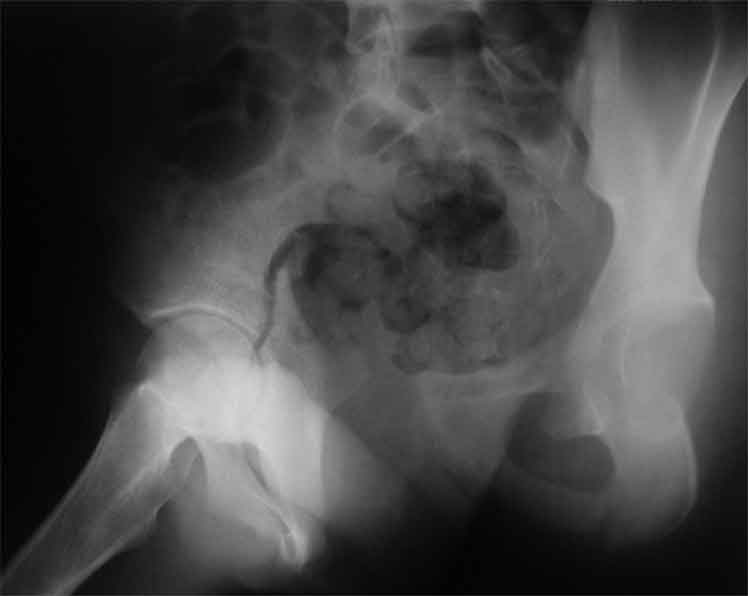

Уважаемые коллеги, сложный случай, интересует ваше мнение. Травма 2 месяца назад, в результате ДТП. При поступлении в лечебное учреждение по м/ж выполнено формирование культи на уровне в/3 левого бедра по (травматический дефект левой н/конечности), в послеоперационном периоде раневая инфекция, остеомиелит - экзартикуляция.

Повреждение таза лечилось консервативно. Интересует ваше мнение по поводу тактики лечения, попытаться свести аппаратом, а потом открытый этап (каким доступом/доступами)? другие варианты? С уважением Максим Агалаков